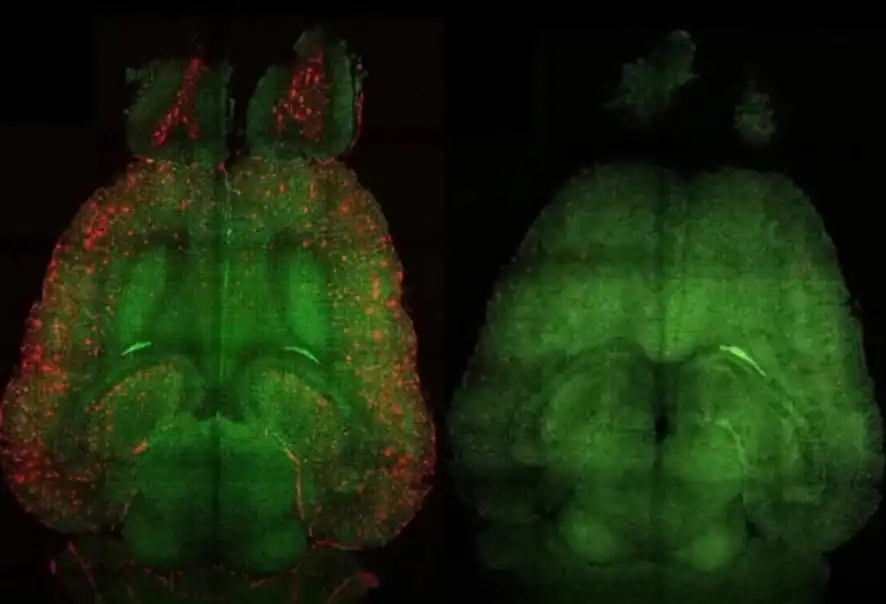

Pesquisadores anunciaram um avanço considerado promissor no combate ao Doença de Alzheimer. Estudos experimentais conseguiram remover placas beta-amiloides do cérebro, estruturas tóxicas associadas à progressão da doença.

Nos experimentos, cientistas observaram que a remoção dessas estruturas levou a melhora em sinais neurológicos e a uma recuperação parcial da atividade cerebral nos modelos analisados.